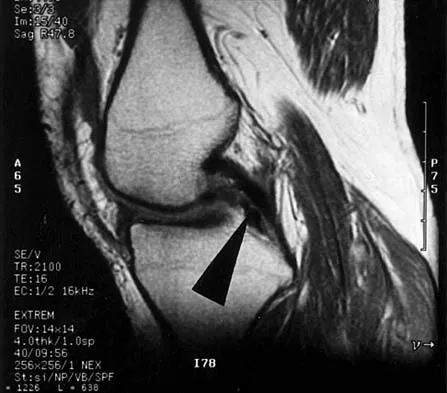

Figures 31a and 31b show the T1- and T2-weighted MRI scans of a patient's knee joint. What is the most likely diagnosis?

Explanation

Figure 39 shows the sagittal T1-weighted MRI scan of a 27-year-old man who twisted his knee 2 weeks ago. The arrow is pointing to

Explanation